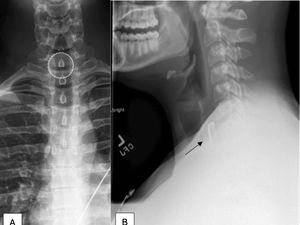

Seorang pria di China menggegerkan jagat maya setelah ketahuan ada sumpit logam sepanjang 12 cm dari tenggorokannya. Benda itu 8 tahun bersarang di tenggorokan.